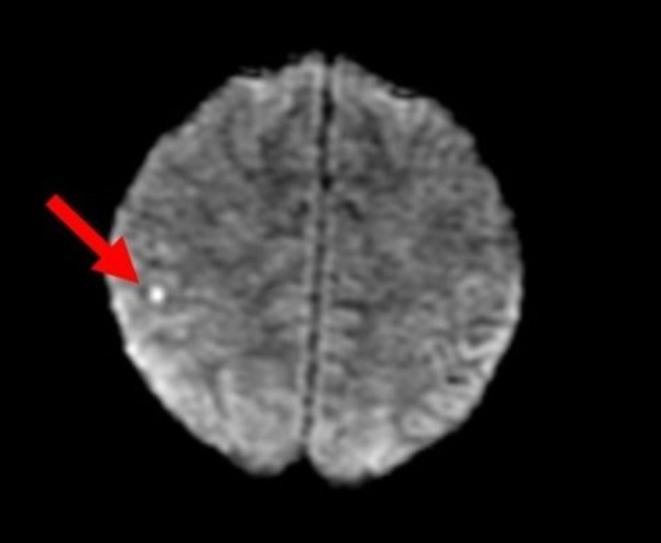

Acute Cerebrovascular Accident, Renal Failure, and Thrombotic Microangiopathy in a 27-Year-Old Male With Malignant Hypertension.

Hypertensive emergency is an acute, significant elevation of blood pressure accompanied by end-organ damage. We present a case of a 27-year-old gentleman who acquired multiple complications of hypertensive emergency, including renal failure and microangiopathy. This highlights the diverse complications of hypertensive emergency and reviews guideline-based recommendations for management.